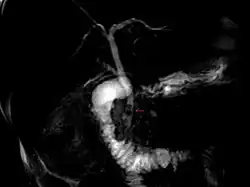

MRCP obraz. Choledocholitiáza. Dva žlučové konkrementy (šipka) v distální části ductus choledochus.

2. Posthepatální ikterus (obstrukční, cholestatický). Problém/porucha způsobující posthepatální ikterus se nachází „za játry“ (z latinského post, tj. za a řeckého hepar, tj. játra). Vzniká jako následek poruchy vylučování konjugovaného bilirubinu do střeva (žluč se v důsledku překážky nedostává žlučovými cestami do střeva). Překážka znemožňující tok žluči do střeva může být lokalizována v játrech (intrahepatální cholestáza) nebo ve žlučových cestách mimo játra (extrahepatální cholestáza). Příčinou intrahepatální cholestázy je např. onemocnění zvané primární biliární cirhóza. Příčinou extrahepatální cholestázy je nejčastěji uzávěr žlučových cest konkrementem nebo stlačení (komprese) žlučových cest zhoubným nádorem slinivky břišní (hlava slinivky břišní „sousedí“ se žlučovými cestami). V séru je zvýšena hladina konjugovaného bilirubinu. Konjugovaný bilirubin lze prokázat i v moči, moč má tmavou barvu. Při úplné neprůchodnosti (obstrukci) žlučových cest se do střeva nedostává žádná žluč, stolice je odbarvená (acholická), urobilinogen nevzniká a v moči je tedy negativní.[34][35] Alkalická fosfatáza a gama-glutamyltransferáza jsou zvýšené.[9]